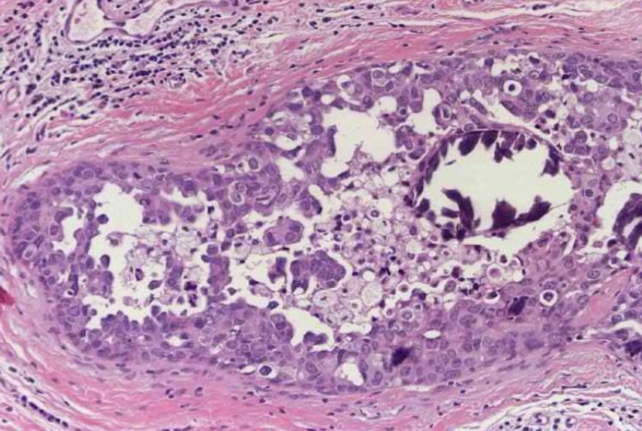

Liquefactive necrosis

Anaplasia